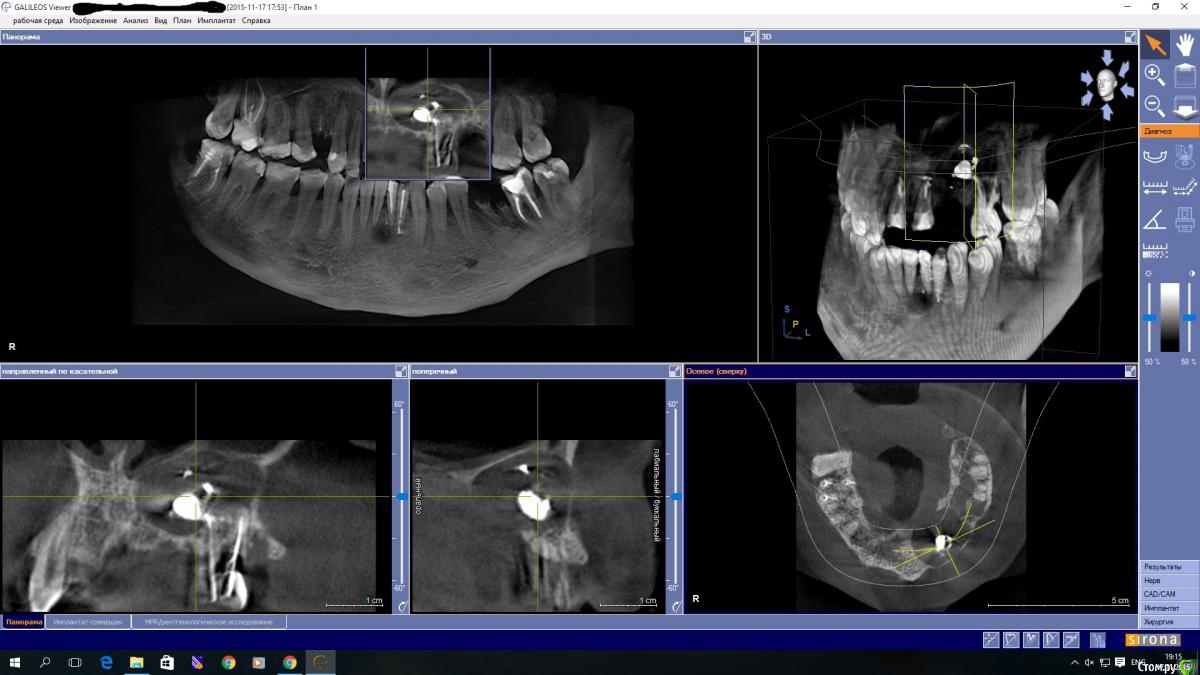

Ponchik Опубликовано 17 ноября, 2015 Поделиться Опубликовано 17 ноября, 2015 (изменено) Пациента ничего не беспокоит. В анамнезе травма 2 сегмента 7 лет назад. Пришел с целью протезирования. Ортопед удалили 22 и направил кисту убрать. Сделали прицельный.Потом захотелось КТ. КТ вышло не очень, но общее представление составить можно. Появились вопросы. На сколько велика вероятность встречи с синусом? Стоит делать амбулаторно? Опыт до этого - цистэктомии в пределах 1-2 зубов. Думаю куда направить. Изменено 17 ноября, 2015 пользователем Ponchik Ссылка на комментарий

andrey_1965 Опубликовано 2 декабря, 2015 Поделиться Опубликовано 2 декабря, 2015 Так и поступлю. Только осталось придумать куда. Москва-то большая.Не подскажете куда лучше? Бюджетный вариант. Если можно в личку.Если совсем бюджет-то только в институт на кафедру,оформлять как "учебный процесс".Совсем без оплаты не обойдется,но это будет самая минимальная стоимость.Свяжитесь с кафедрами Ломакина или Дробышева-лучше самому поехать с ОПТГ,КТ.Пообщайтесь,может получится включить в учебный план. Ссылка на комментарий